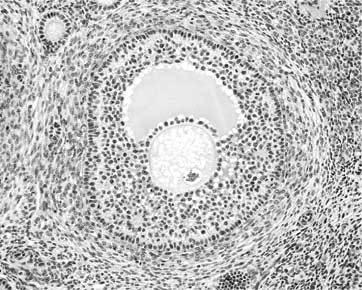

В яичниках находятся небольшие шаровидные образования, называемые «фолликулами». В каждом фолликуле содержится одна женская половая клетка, которую называют яйцевой клеткой или сокращенно – яйцеклеткой. Яйцеклетка окружена двумя соединительнотканными оболочками и слоем клеток, обеспечивающим ей не только защиту, но и доставку питательных веществ из жидкости, заполняющей фолликул. Клеточная оболочка яйцеклетки поэтично называется «лучистым венцом», а наружная соединительнотканная оболочка, находящаяся под лучистым венцом, называется «блестящей». Блеск оболочке придают содержащиеся в ней гликопротеины – белки, имеющие в составе молекулы сахаридные остатки.

Яйцеклетка не плавает в фолликуле, а располагается не выступе, который называется «яйценосным холмиком» или «яйценосным бугорком». Фолликул содержит клетки, способные вырабатывать гормоны. Это не просто хранилище яйцеклетки, а эндокринный орган.

Фолликул